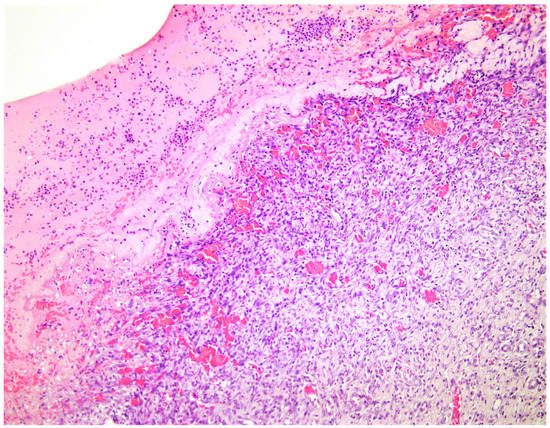

—fibrin clot,

—granulation tissue,

—epithelium,

—fibrotic tissue.